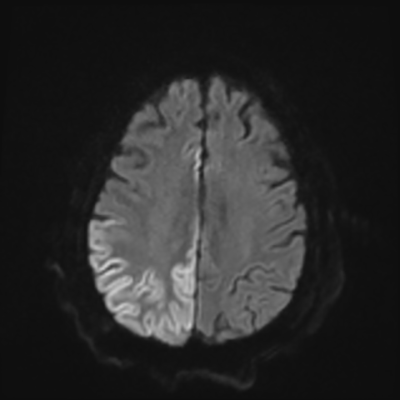

You come back the next day and see how things are going. The patient's electrographic record has shown a moderate encephalopathy (diffuse slowing, disorganization) with frequent right posterior quadrant delta slowing. Based on this result, and an adequately improved clinical examination, you give the okay to proceed with obtaining an MRI of his brain. This is shown below.

MRI brain (DWI)